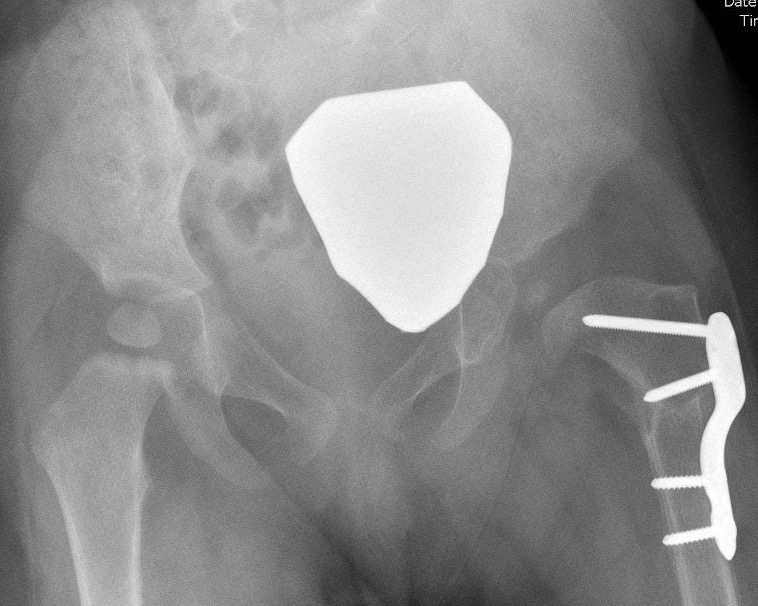

2. Femoral Varising Derotation Osteotomy (VDRO)

- shortening indicated if difficulty reducing the hip

- derotation if femoral anteversion > 50 degrees

Technique

Synthes Pediatric Proximal Femur Offset Plate Technique PDF

Youtube open reduction and VDRO video

Measure planned correction

- preoperative: 150 degrees

- postoperative: 120 degrees

Separate lateral approach

- elevate vas lateralis +/- release proximally with L shaped release

- open and protect periosteum with Homan retractors

- mark distal and proximal femur with drill holes to check rotation

- place wires up femoral neck short of physis

- use plate to mark osteotomy site

Osteotomy with microsagittal saw 1 cm below lesser tuberosity

- may need to shorten

- +/- adjust version

- apply plate and fix with screws